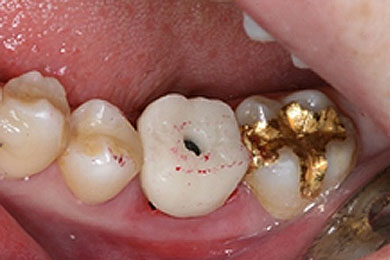

아랫부분에 틀니를 사용하시다가 불편하셔서 방문하셨습니다.

2021.04

치아가 없는 아랫부분에 네비게이션(가이드)임플란트로, 기존에 뺐다 꼈다 했던 불편한 틀니 대신 좀 더 음식을 잘 씹을 수 있는 임플란트로 진행하였습니다.